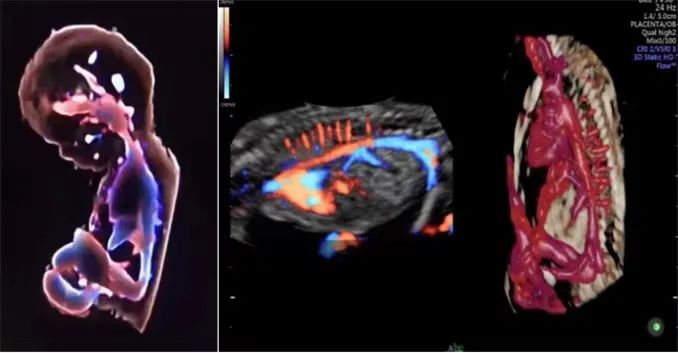

“煊流技术”可真实呈现脐带、胎盘血流,对于深部小血管的立体结构显示极具优势,在评估血管分布或灌注状态时,如同采用血管造影模式。提升产前检查的诊断质量和效率。

“煊彩成像”技术:—血流轮廓剪影。